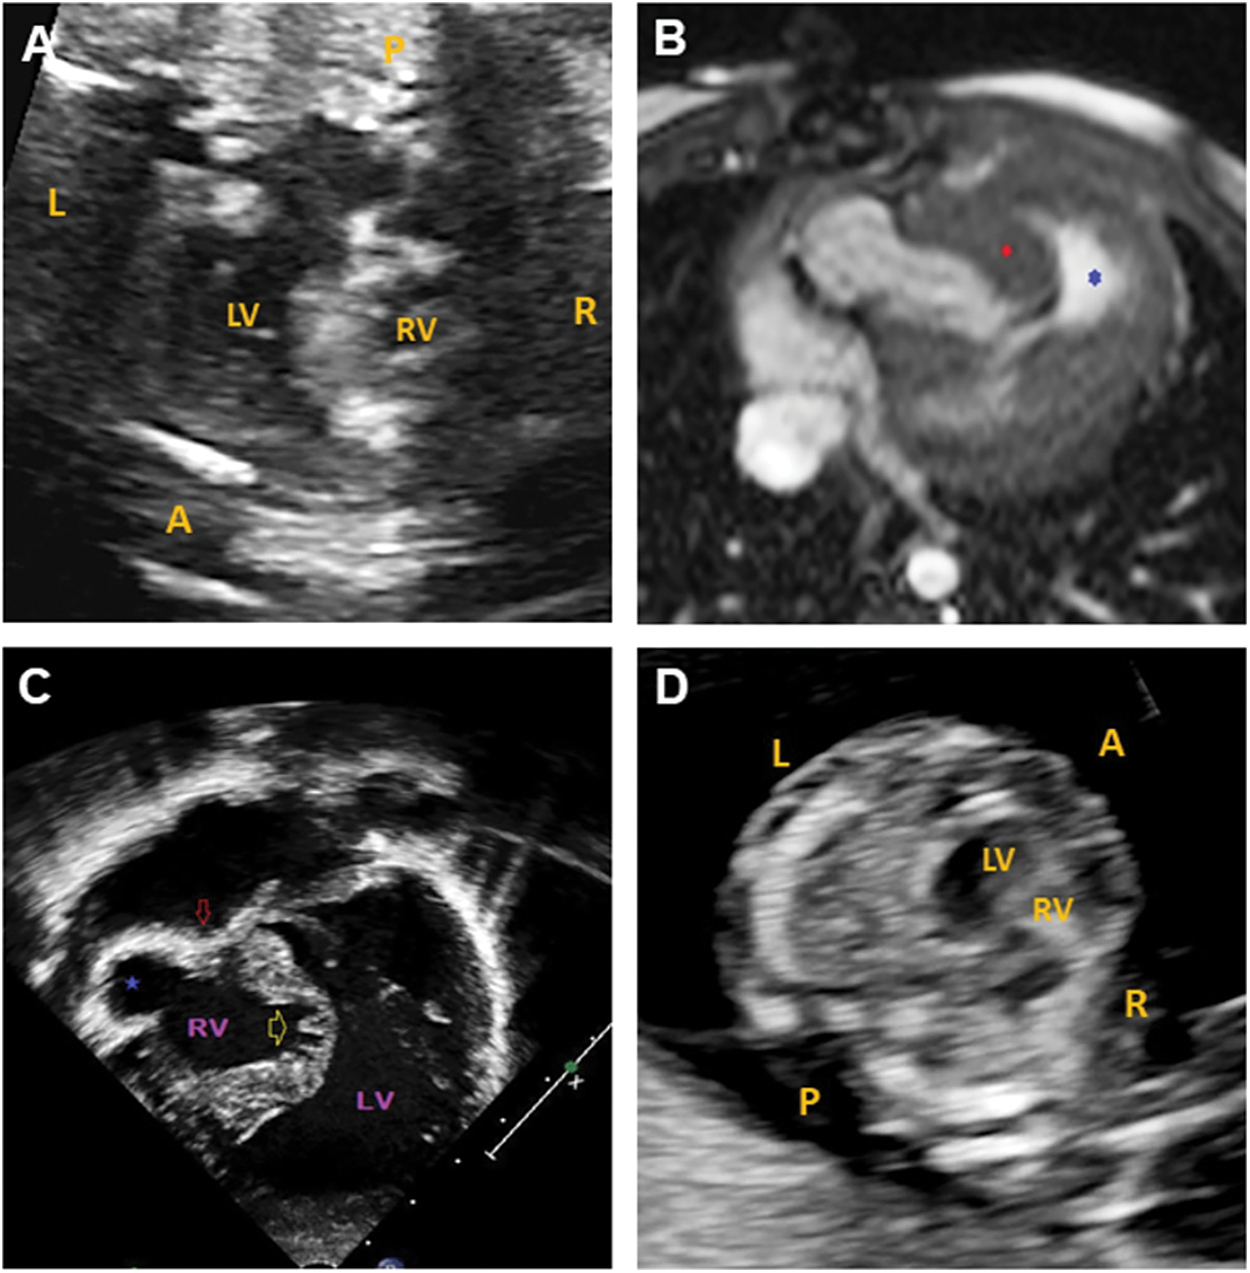

The proband was the product of the first pregnancy of a healthy non-consanguineous couple of European descent. A fetal echocardiogram at 20 weeks 6 days gestation done on the mother showed severe pulmonary valve stenosis, hypoplastic tricuspid valve, large muscular VSD, bilateral hypoplastic main pulmonary arteries and critically hypoplastic and dysmorphic RV (multilobular parts) (26-week fetal echocardiogram, Fig. 1A, and supplementary video S1).

Figure 1: Cardiac imaging for the paediatric case and fetal sibling. (A) 26-week fetal echocardiogram for the paediatric patient showing a hypoplastic RV. (B) Cardiac MRI for the paediatric patient at birth. Axial balanced steady state gradient echo (TRUFISP). Severe tricuspid valve stenosis with RV anterior free wall ballooning (blue star) and hypertrophied moderator band (red diamond). (C) Echocardiography for the paediatric patient at birth. Apical view with severe tricuspid stenosis (red arrow), RV anterior free wall ballooning (blue star), and atrophic and trabecular inter-ventricular septum. (D) 13-week fetal echocardiogram showing a hypoplastic RV in the fetal sibling. L: left, R: right, A: anterior, P: posterior, LV: left ventricle, RV: right ventricle

Delivery was at term and uncomplicated. The patient’s birthweight was 2.85 kg (3–10th centile). Postnatal echocardiography and MRI (Figs. 1B and 1C) confirmed the antenatal diagnosis with the addition of coronary sinusoids (RV) and an aberrant right subclavian artery with left aortic arch.

The couple’s second pregnancy was naturally conceived and NT ultrasound at 12 weeks gestation was 3.1 mm. Enhanced first trimester screening done subsequently showed an increased risk for Trisomy 21 (1 in 12 at term). Given the history of a child with complex CHD, the family was referred for fetal ultrasound and echocardiography at 13 weeks gestation. The fetal imaging showed hypoplastic, non-apex forming RV and hypoplastic tricuspid valve with minimal, monophasic inflow (Fig. 1D and supplementary videos S2–S4). No VSD was present. Normal left-sided structures were observed.